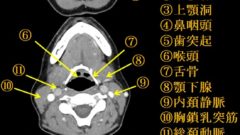

胸管

(77am50、76am64、71am57、68pm54、66.10)

下半身と左上半身のリンパを集めるリンパ管(残りは右リンパ本管へ)

第二腰椎付近から始まり、左鎖骨下静脈と内頚静脈の合流点(左静脈角)で静脈に入る